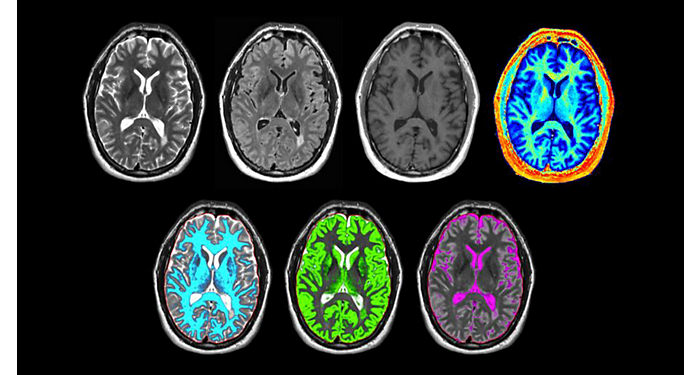

70% of radiologists consider neuro indications to be challenging, mostly due to a lack of appropriate imaging and visualization techniques¹. Philips aims to provide the best possible diagnostic clarity and treatment guidance for all patients with neurological disorders. By leveraging our dStream digital platform, this year, we are introducing, a set of novel imaging and visualization strategies. These may empower you to resolve complex neuro questions with more certainty, as well as unlock new neuro territories in advanced Neurofunctional applications. This is a key step towards elevating neuro diagnostics and ultimately touching more lives with MR imaging. ¹ TMTG Market Survey 2016

New neuro applications

Take a look at our other neuro applications